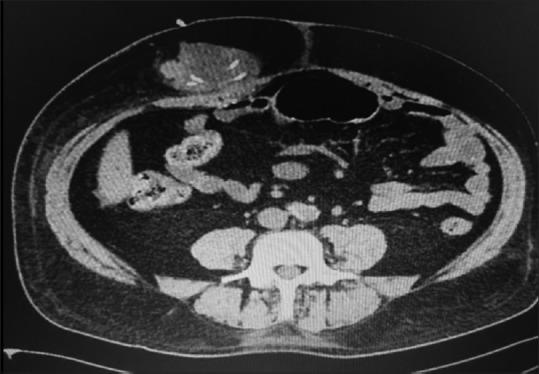

We describe an atypical case of VP shunt postoperative by normal pressure hydrocephalus. After well-documented proper positioning of the distal catheter into the intraperitoneal cavity, it protruded into the subcutaneous space. Even on a new documented satisfactory abdominal tomography, this catheter migrated back again to the subcutaneous tissue.

我们描述了一例常压性脑积水VP分流术后的非典型病例。在有充分记录证明远端导管正确置入腹腔后,它却突出到皮下间隙。即使在新的记录显示腹部断层扫描结果令人满意的情况下,该导管再次迁移回皮下组织。